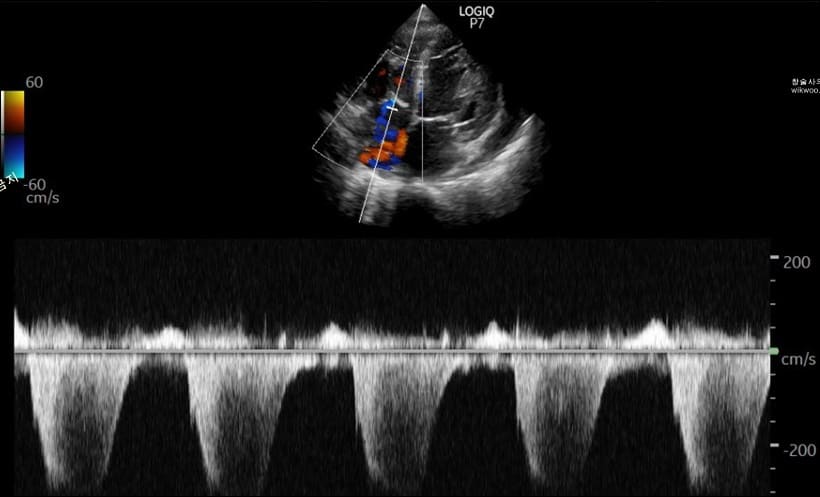

심장초음파 검사는 인체에 해롭지 않은 초음파를 심장에 보내어 반사돼서 돌아오는 초음파를 이용하여 영상을 만들어 심장의 구조와 기능을 분석하는 검사 기법입니다.

몸속으로 의료 기구를 삽입하지 않고 심장의 내부 구조와 기능, 움직임 등을 눈으로 직접 볼 수 있으며, 임산부나 유아도 안심하고 검사할 정도로 부작용이 없이 안정적인 검사 방식입니다.